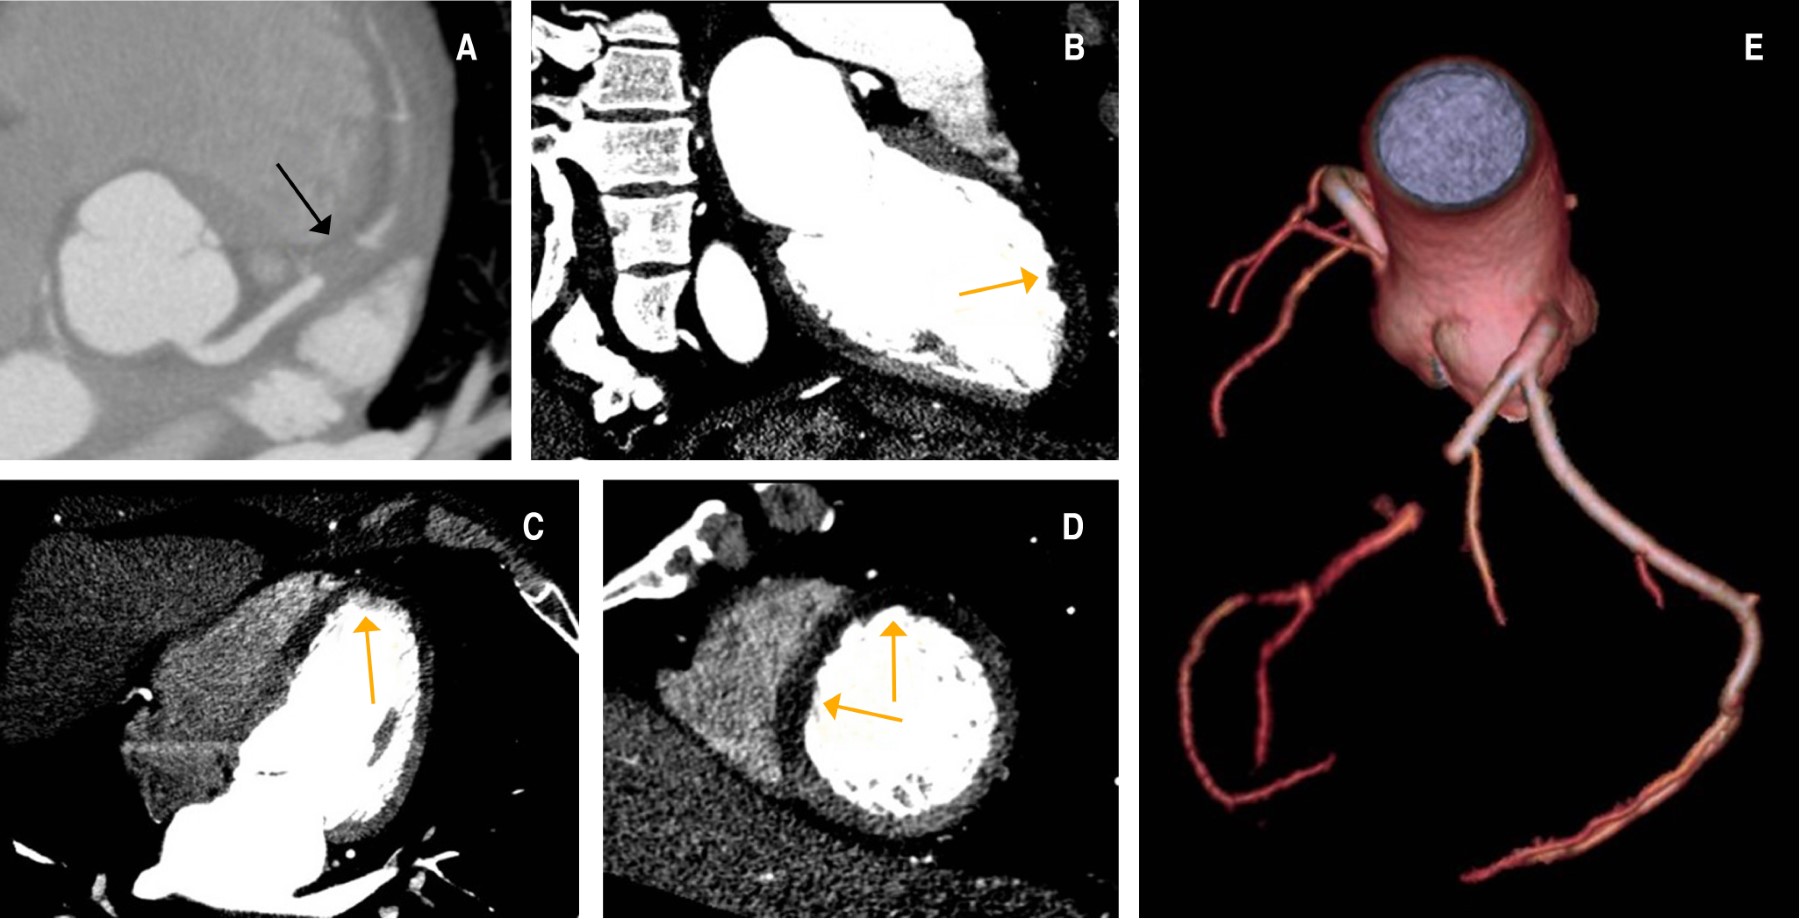

Divertículo ventricular congénito izquierdo aislado en adulto: un hallazgo inusual en infarto de miocardio asociado a cocaína

El divertículo ventricular congénito izquierdo (DVCI) consiste en una bolsa de salida de endocardio, miocardio y pericardio, que a menudo se presenta como una proyección de la pared libre del ventrículo, con un cuello estrecho que conecta la cavidad con el ventrículo propiamente dicho. Aunque a menudo se asocia con otras anomalías congénitas cardiacas y extracardiacas, también puede presentarse solo, como un hallazgo incidental en pacientes adultos. Debido a su baja prevalencia general y variabilidad en la presentación, aún no se ha definido un tratamiento estandarizado. Presentamos el caso de un paciente adulto con infarto de miocardio (IM) asociado a cocaína, en el que se evidenció un DVCI septal mediante angio-TC coronaria. Se descartaron otras anomalías cardiacas y el paciente respondió bien al tratamiento médico tras el cateterismo cardiaco; por lo que se prefirió el seguimiento médico y no la cirugía.

Figura 2